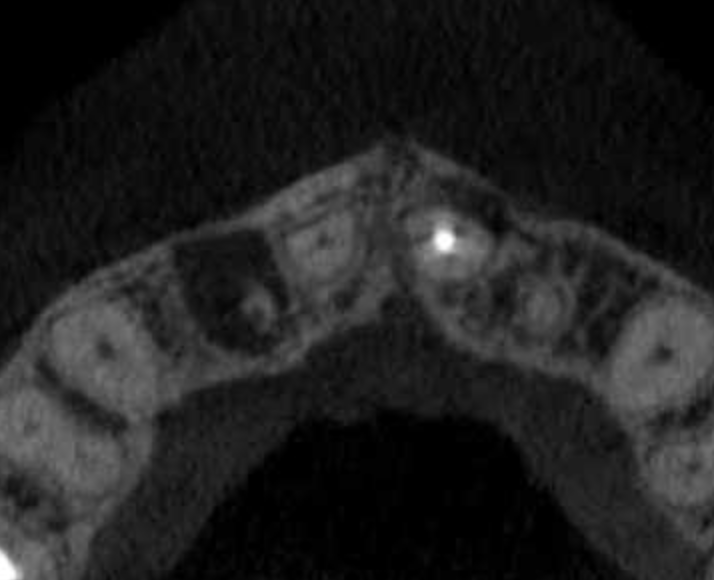

Pulpotomía biodentine + reco preendio